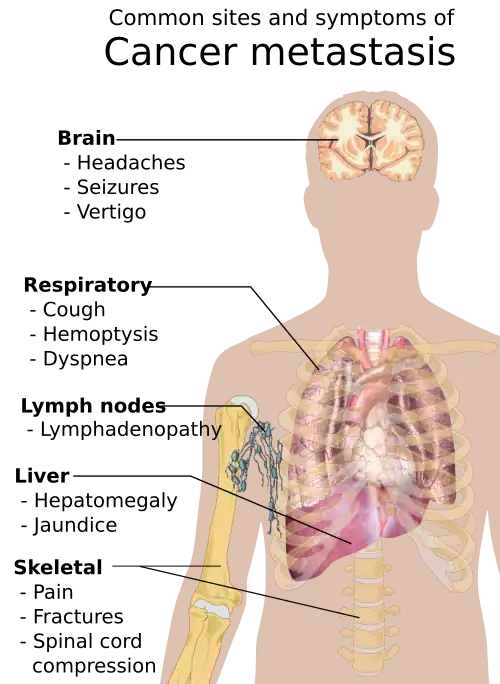

Metastasis is the spread of cancer to other locations in the body. The dispersed tumors are called metastatic tumors, while the original is called the primary tumor. Almost all cancers can metastasize.[40] Most cancer deaths are due to cancer that has metastasized.[41]

Metastasis is common in the late stages of cancer and it can occur via the blood or the lymphatic system or both. The typical steps in metastasis are:

Different types of cancers tend to metastasize to particular organs. Overall, the most common places for metastases to occur are the lungs, liver, brain, and the bones.[40]